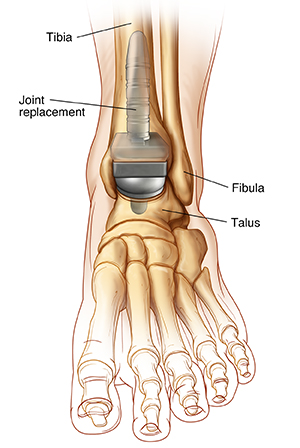

The ankle joint

A joint is a place in the body where bones meet. The ankle joint is two joints. One is called the true ankle joint. The shinbone (tibia), fibula (the smaller bone in the lower leg), and talus bones make up this joint. This joint is replaced during this surgery. Parts of the tibia and talus are replaced.

This surgery will be done by an orthopedic surgeon. The surgeon will make a cut (an incision) through the skin and muscle of your ankle. An incision may also be made on your foot. The damaged parts of your shinbone and talus will be removed. The artificial joint components will be attached to your shinbone and talus. A special type of cement may be used to hold them in place. A piece of plastic may be put between the new metal joint pieces. This is so they can glide easily against each other.